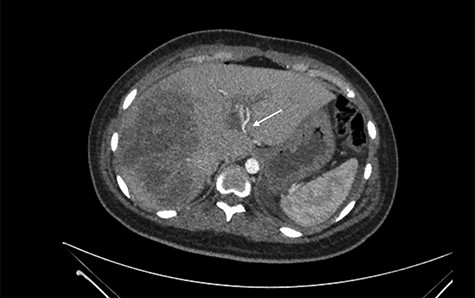

She was referred to our center on postoperative Day 4 due to progressive jaundice and encephalopathy. A triphasic contrast-enhanced abdominal computed tomography (CT) was done revealing a right liver lobe infarct, absence of the right and left hepatic arteries (Fig. 1), presence of an accessory left hepatic artery from the left gastric artery (Fig. 2) and right portal vein thrombosis with extension to the main portal vein (Fig. 3).

Main portal vein thrombosis (white arrow) on portal phase of the triphasic contrast-enhanced abdominal CT.